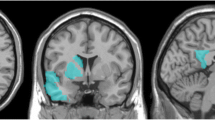

This study investigated brain microstructural changes in patients with amnestic mild cognitive impairment (aMCI) by retrospectively analyzing neurite orientation dispersion and density imaging (NODDI) data with machine learning algorithms.

A total of 26 aMCI patients and 24 healthy controls (HC) underwent NODDI magnetic resonance imaging (MRI) examinations. The NODDI parameters including neurite density index (NDI), orientation dispersion index (ODI), and volume fraction of isotropic water molecules (Viso) were estimated. Machine learning algorithms such as K‑nearest neighbor (KNN), logistic regression (LR), random forest (RF), and support vector machine (SVM) were used to evaluate the diagnostic efficacy of NODDI parameters in predicting aMCI. The differences in the NODDI parameter values between the aMCI and HC groups were analyzed using the independent sample t‑test, False discovery rate (FDR) correction was used for multiple testing. After adjusting for age, sex, and educational years, partial correlation analysis was used to evaluate the relationship between NODDI parameters and clinical cognitive status of aMCI patients.

The NDI, ODI, and Viso values of white matter (WM) and gray matter (GM) structure templates combined with the KNN, LR, RF and SVM machine learning algorithms accomplished the discrimination between aMCI and HC groups. The NDI and ODI values decreased (p value range, < 0.001–0.042) and Viso values increased (p value range, < 0.001–0.043) in the aMCI group compared to the HCs. The NDI, ODI, and Viso values of the WM and GM structure templates with significant differences were significantly correlated with mini-mental state examination (MMSE) and Montreal cognitive assessment (MoCA) scores.